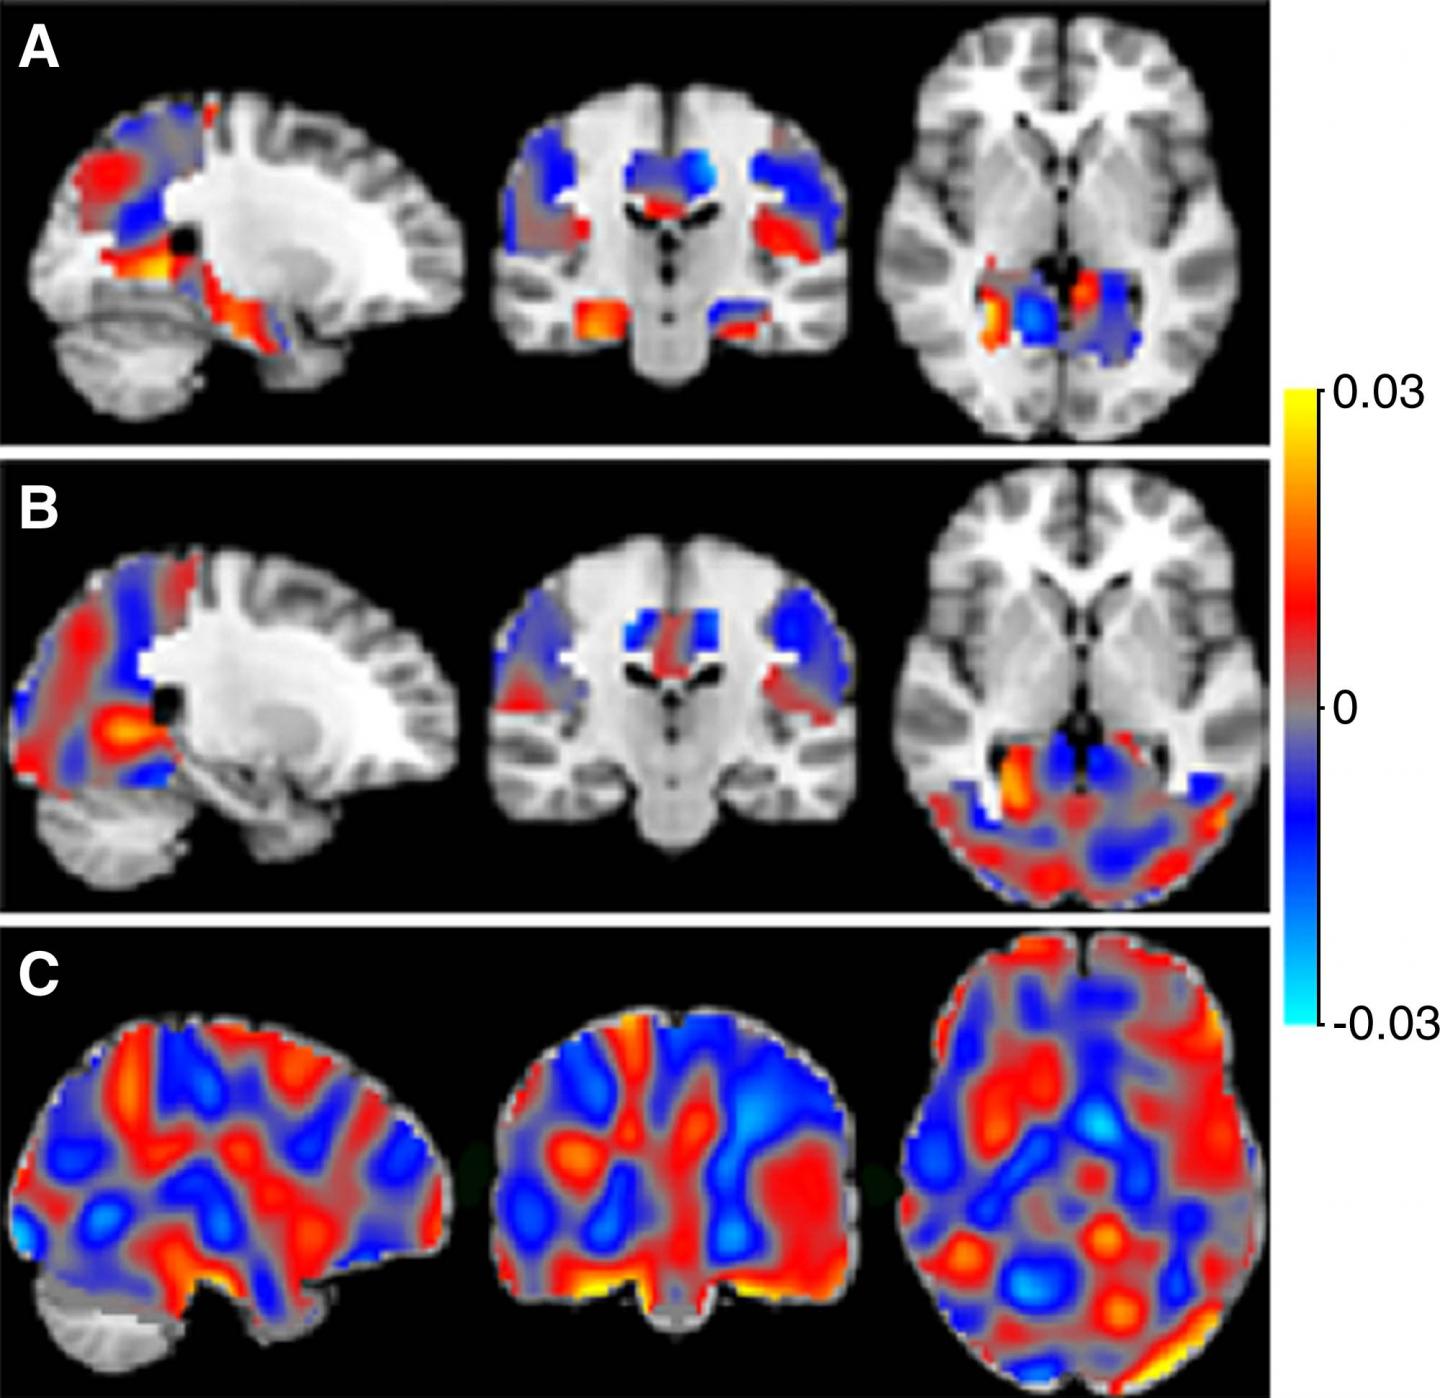

For the new study, the researchers applied machine learning methods to special type of MRI called arterial spin labeling (ASL) imaging. ASL MRI is used to create images called perfusion maps, which show how much blood is delivered to various regions of the brain.

The automated machine learning program is taught to recognize patterns in these maps to distinguish among patients with varying levels of cognitive impairment and predict the stage of Alzheimer's disease in new (unseen) cases.